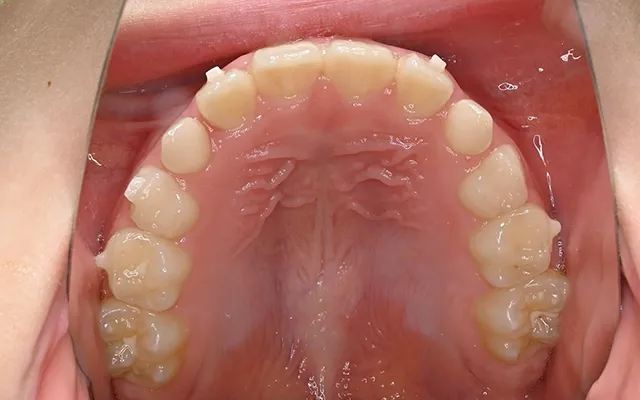

- AFTER

-

| 治療内容 | インビザラインファーストによる矯正治療 |

| 費用 | 528,000円 |

| 期間 | 5か月 |